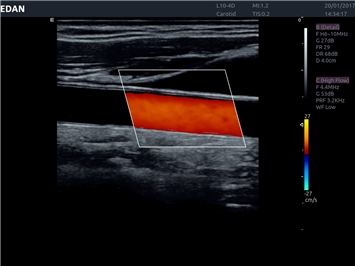

EDAN Acclarix LX4 представляет собой инновационную ультразвуковую систему, построенную на усовершенствованной платформе Acclarix. Сочетание высокого качества визуализации с интеллектуальным рабочим процессом делает эту систему оптимальным выбором для клиник, ценящих эффективность и экономичность.

• Сосудистой диагностики

• Автоматическое измерение толщины интима-медиа

Цветовой допплер:

Да

IMT (Intima Media thickness):